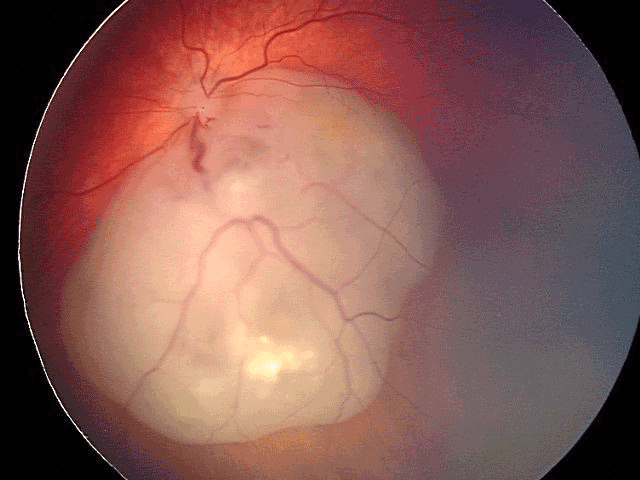

Mélanome choroïdien Diagnostic du mélanome choroïdien Il s'agit de la tumeur intraoculaire primitive la plus fréquente de l'adulte. Le mélanome uvéal peut toucher la choroïde (site le plus fréquent que nous décrirons ici), le corps ciliaire ou l'iris. Son incidence annuelle est d'environ 500-600 nouveaux cas par an en France. L'âge médian au diagnostic est de 62 ans mais il peut survenir à tout âge. Il touche généralement les sujets caucasiens, avec un surrisque parmi les personnes ayant les yeux bleus, pour des raisons non encore élucidées. Le diagnostic est clinique, ce qui est une singularité en oncologie, car l'obtention d'une preuve histologique par biopsie invasive exposerait à un risque de dissémination orbitaire. Il repose sur l'examen du fond d'œil et l'échographie oculaire. On observe une lésion choroïdienne en relief (Figures 1 et 2), de morphologie en dôme ou en champignon (Figure 3). La lésion est souvent pigmentée mais peut également être achrome (Figures 4 et 5), ce qui doit alors faire suspecter une métastase choroïdienne, avec réalisation d'un bilan d'extension complet, à la recherche d'une néoplasie primaire ayant métastasé à l'œil. Un décollement de rétine exsudatif peut être présent (Figure 6). Une hémorragie intravitréenne peut s'associer et masquer la tumeur. Ces deux présentations impliquent de devoir réaliser systématiquement une échographie oculaire en cas de décollement de rétine exsudatif sans déhiscence retrouvée, ou en cas d'hémorragie intravitréenne. En effet, une éventuelle chirurgie intraoculaire par vitrectomie sur un mélanome uvéal méconnu peut entraîner une dissémination tumorale.

Figure 1 Mélanome choroïdien situé à proximité de l'émergence intraoculaire du nerf optique.